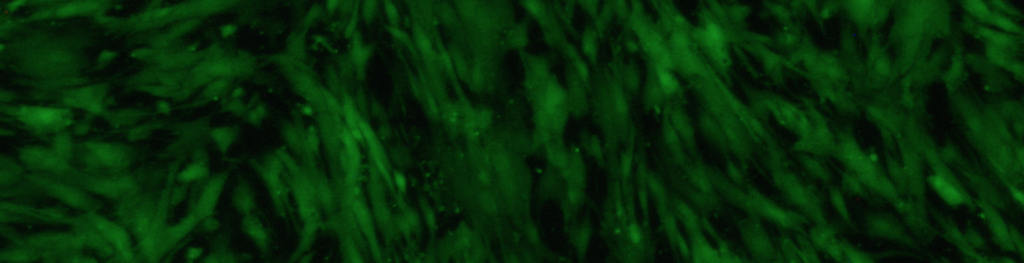

D&P Bioinnovations, LLC is a regenerative medicine startup focused on repairing damaged organs. We are developing an implantable, bioresorbable "off-the-shelf" medical device to regenerate a damaged esophagus (organ providing food to the stomach). This device will address a $750 million U.S. annual market to treat advanced Barrett's Esophagus, esophageal cancer, birth defects of the esophagus, and fatal cases of caustic ingestion.